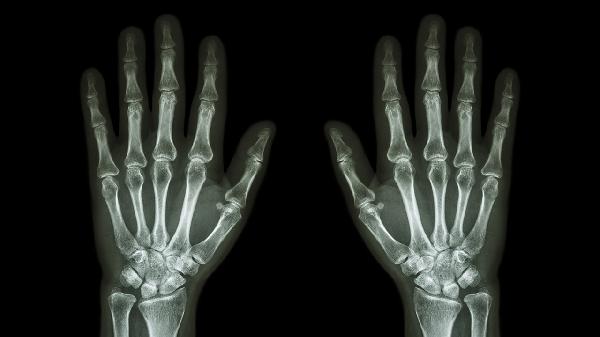

中老年人群常见退行性关节病变,晨起可出现关节僵硬伴疼痛,活动后减轻但过度使用会加重。X线检查可见关节间隙狭窄或骨赘形成。治疗包括关节保护训练、物理治疗,药物可选塞来昔布胶囊、硫酸氨基葡萄糖胶囊、双醋瑞因胶囊等。

自身免疫性疾病典型表现为对称性小关节晨僵超过1小时,可能伴随关节肿胀变形。血液检查可见类风湿因子阳性。早期干预可延缓病情,常用药物有甲氨蝶呤片、来氟米特片、艾拉莫德片等,需定期监测肝功能。